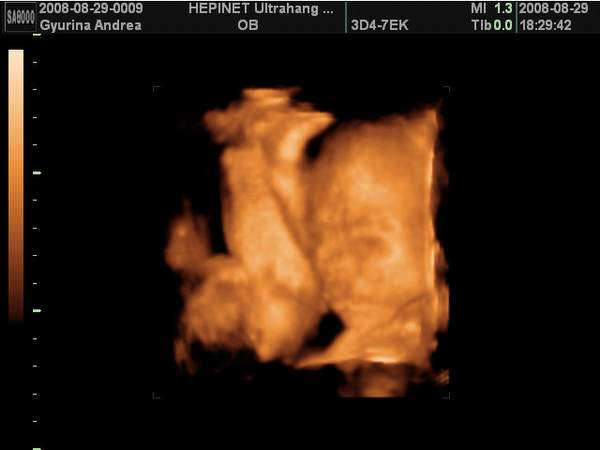

Én pénteken voltam 4D UH-on és végre megláttam a picurkám pofiját, ami szakasztott olyam, mint a nagyfiamé volt pinduri korában. Hát igen, van egy "nagy" fiam és lesz egy "kis"fiam is. Egyáltalán nem bánom, hogy fiú lett, majd a harmadik tuti lány lesz... :D

Dobok róla néhány képet, ha nem baj.

Kép Térd szaglászás...

Kép Nagyon töri valamin a buksiját...

Kép